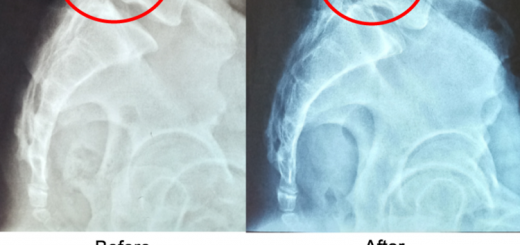

Hunching 55 year old